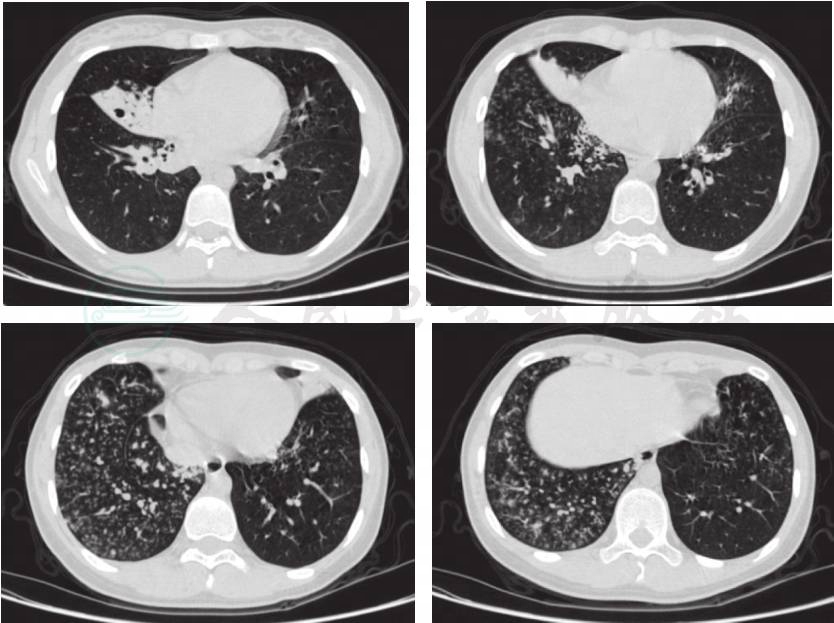

入院后完善相关检查,考虑支气管扩张患儿肺部铜绿假单胞菌等革兰氏阴性杆菌定植后感染较多见,经验性予头孢他啶抗感染,同时予大环内酯类抗生素口服抗感染治疗。入院后查血常规+CRP正常,血沉45mm/h(升高),LDH 847U/L(升高),肝肾功能、血清铁蛋白及降钙素原正常,呼吸道病毒抗体、肺炎支原体、衣原体、嗜肺军团菌阴性,痰培养呼吸道正常菌丛生长,未检出明确病原菌。入院后完善胸部HRCT检查,所见(图1)左肺上叶舌段、下叶及右肺下叶可见散在粟粒状渗出影及“树芽征”,右肺中叶见片状渗出影,右肺中、下叶部分支气管扩张、管壁增厚,部分管腔内见黏液栓。根据胸部CT表现,临床思考:①两肺散在粟粒状渗出影和小结节影以及“树芽征”,提示累及细支气管的炎症渗出或分泌物堵塞,考虑到患儿同时存在慢性鼻窦炎,需注意弥漫性泛细支气管炎的可能,予以完善副鼻窦CT及冷凝集试验;②存在结核感染可能,应详细询问排除结核接触史,并完善结核感染T细胞测定、肺泡灌洗液抗酸染色及结核分枝杆菌DNA定量等检查;③真菌感染表现不典型,可行真菌1,3-β-D葡聚糖试验辅助诊断;④注意肺囊性纤维化、原发性纤毛运动障碍及先天性免疫缺陷等少见病的可能,完善细胞体液免疫功能、血淀粉酶检测,亦需进行副鼻窦CT检查,同时在支气管镜检查中进行支气管黏膜活检电镜检查;⑤应继续完善病原学的检测,予以支气管镜检查及支气管肺泡灌洗。患儿入院第4天行支气管镜检查,术中发现患儿气道结构正常,右主支气管、右肺中叶及左主远端支气管内较多白色黏稠分泌物附着,阻塞部分支气管开口,予以吸引干净后在上述支气管开口处做支气管肺泡灌洗,回收灌洗液送培养和相关病原学检测。并分别在右肺中叶支气管、左主远端支气管开口取活检,送电镜纤毛检查。入院第5天,患儿咳嗽减轻,咳痰减少,肺部啰音减少。但前述各项检查中,除外副鼻窦CT平扫(图2)示全鼻窦炎,窦内分泌物密度较高,其余血清学检查、肺泡灌洗液检查、纤毛电镜检查及基因检查(罕见遗传病基因测序)均未见异常。与患儿及家属充分讨论后,于入院第13天行肺活检术,手术顺利,术后恢复可。肺组织病理检查(右肺)(图3)提示淋巴组织增生相关疾病(滤泡性细支气管炎,部分区域呈淋巴细胞间质性肺炎改变)。同时完善自身免疫疾病抗体全套检查,其中ANA 1:320(阳性),余抗体阴性。入院第19天患儿病情稳定出院,出院后长期口服小剂量红霉素抗炎,口服细菌溶解产物调节免疫功能,雾化吸入乙酰半胱氨酸化痰,并嘱每日体位引流及震动正压通气装置呼吸锻炼2~3次,风湿科及呼吸科定期随访。目前随访至出院后5个月,期间短时发热2次,未予特殊处理自行恢复,咳嗽咳痰好转,近2个月体位引流排痰量较前减少,活动耐力较前增加,随访6分钟步行试验达年龄预计值81.8%(病初56%),生长发育良好。

图1 入院后完善胸部HRCT检查

提示:左肺上叶舌段、下叶及右肺下叶可见散在粟粒状渗出影及“树芽征”,右肺中叶见片状渗出影,右肺中、下叶部分支气管扩张、管壁增厚,部分管腔内见黏液栓

诊断依据:①临床表现:间断发热、咳嗽、咳痰,肺部听诊有湿啰音;②肺HRCT:左肺上叶舌段、下叶及右肺下叶可见散在粟粒状渗出影及“树芽征”。右肺中、下叶部分支气管扩张、管壁增厚,部分管腔内见黏液栓;③肺组织病理检查(右肺)提示淋巴组织增生相关疾病(滤泡性细支气管炎,部分区域呈淋巴细胞间质性肺炎改变)。

胸部X线表现为双侧小结节和网状影,伴有胸腔内淋巴结肿大。HRCT表现为小叶中心性结节影及磨玻璃影。小结节影多为两肺弥漫性分布,结节直径1~12mm,多数3mm,由于细支气管周围淋巴滤泡增生,细支气管管壁增厚,管腔阻塞扩张,亦可出现树芽征,同时由于管壁淋巴组织增生形成活瓣作用阻塞细支气管腔,也可见薄壁囊性结构形成。磨玻璃影也是常见CT表现,一般呈两肺非肺段性、片状分布。有些病例具有轻度的支气管扩张。少见CT表现包括肺气肿、肺结构扭曲、小叶间隔增厚和支气管血管束增粗。